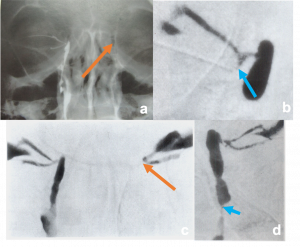

| Invasive Sino-orbital fungal disease[15] | Immunocompromised (mucormycosis)

Imuunocompetent (aspergillosis) |

Severe limitation of EOM with associated chemosis and blepharoptosis.

In mucormysosis, very acute progression of disease with presence of black nasal fliuid, eschar or skin discoloration (characteristic). On fundus examination, CRAO present. In aspergillosis, sub acute progression. |

CT- lobulated soft tissue msses, opacification of paranasal sinuses with high attenuation content with enhancing adjacent orbital soft tissue

T1- low to high intensity T2- marked hypointensity |